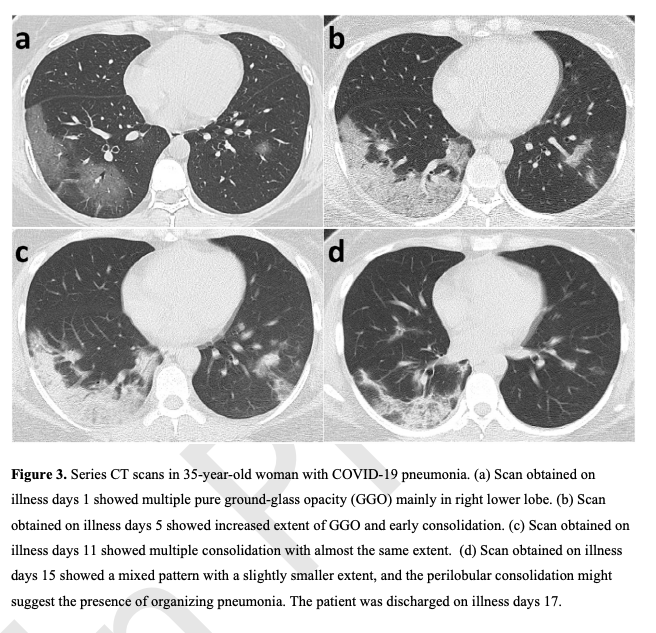

Basic findings on Ground-Glass Opacities and #COVID19.